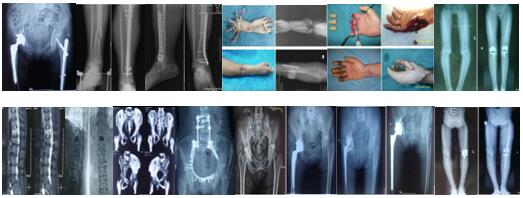

延安大學(xué)咸陽醫(yī)院骨科二病區(qū)(延安大學(xué)醫(yī)學(xué)院第三附屬醫(yī)院,中鐵二十局中心醫(yī)院)是以運動醫(yī)學(xué)、手足顯微外科、關(guān)節(jié)外科、創(chuàng)傷骨科、脊柱外科、骨科康復(fù)為主要研究方向的專業(yè)化科室。現(xiàn)有床位36張,醫(yī)護人員25人,其中主任醫(yī)師1名,副主任醫(yī)師3名,中級職稱4名,醫(yī)學(xué)博士后1名,醫(yī)學(xué)碩士1名??剖覍嵙π酆?、技術(shù)精湛,在咸陽市、陜西省、西北地區(qū)骨科界享有較高的學(xué)術(shù)影響力與知名度。科室擁有一流的手術(shù)設(shè)備、麻醉、頂尖醫(yī)療與專業(yè)醫(yī)護協(xié)作團隊,配備最先進的美國施樂輝關(guān)節(jié)鏡、椎間孔鏡、光學(xué)顯微鏡、麻醉機、呼吸機等一流設(shè)備與儀器,為患者提供生命安全保障。術(shù)后康復(fù)設(shè)備國內(nèi)一流,配有最先進的電磁波治療儀、中頻治療儀、電腦骨傷治療儀、低頻電子脈沖治療儀、紅外線治療儀、定向透藥治療儀、運動治療儀、3D打印個性化定制矯形鞋墊、空氣壓力波等設(shè)備與技術(shù)??剖易o士均經(jīng)專業(yè)的骨科與康復(fù)培訓(xùn),先進的超早期康復(fù)理念,認真負責(zé),技術(shù)過硬,經(jīng)驗豐富??剖揖哂行酆竦目蒲袑嵙?承擔(dān)國家級、省部級、市級課題15項。發(fā)表科技核心論文30篇,SCI論文5篇。多次獲咸陽市科技進步獎與咸陽市自然優(yōu)秀論文,2019年咸陽市骨科斷(肢)指再植創(chuàng)新團隊。

開展手術(shù):1.微創(chuàng)四肢脊柱骨盆骨折(MIPPO、PFNA、髓內(nèi)釘、PVP、釘棒系統(tǒng));2.斷肢(指)再植、拇指再造;3.關(guān)節(jié)置換與翻修、單髁置換;4.關(guān)節(jié)鏡半月板修復(fù)、韌帶重建修復(fù)術(shù)。